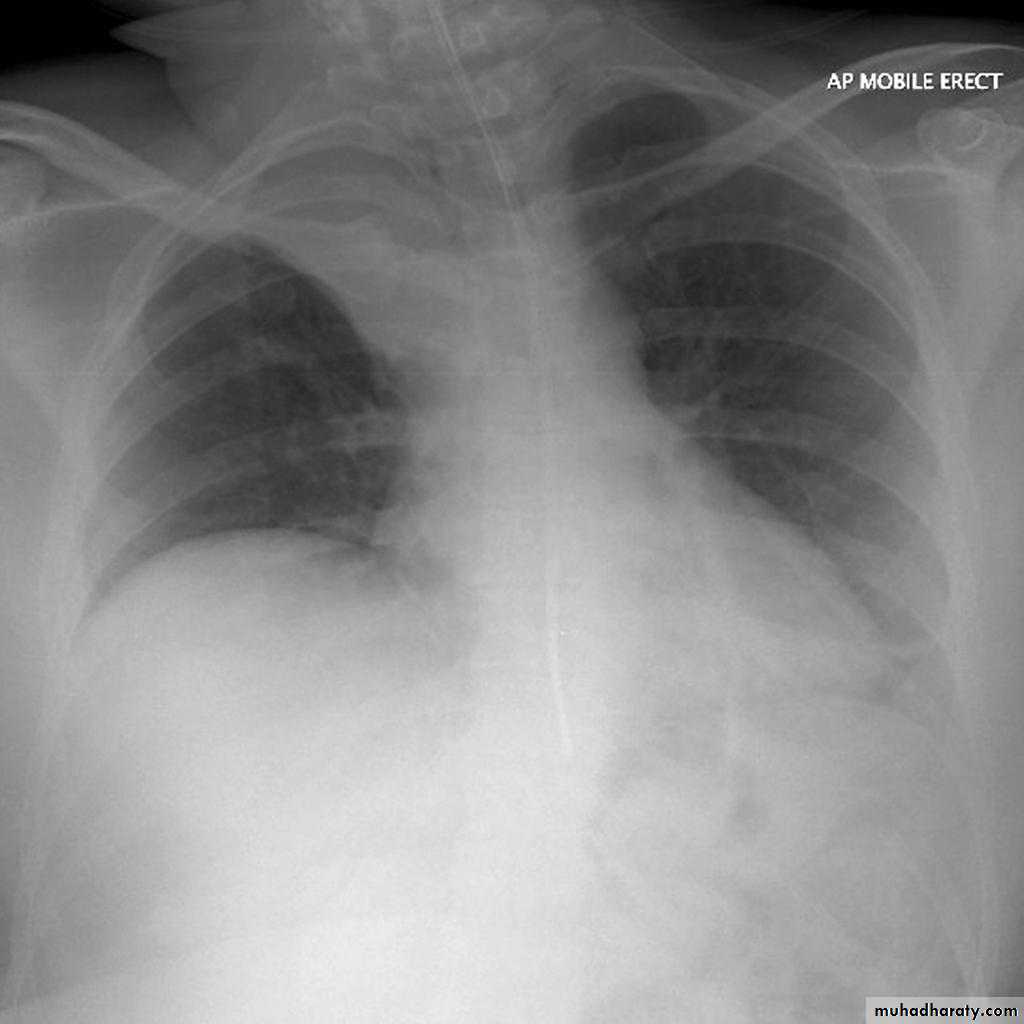

Left lower lobe collapse has distinctive features, and can be readily identified on frontal chest radiographs, provided attention is paid to the normal cardiomediastinal contours. The shadow cast by the heart does however make it harder to see than the right lower lobe collapse

Radiographic features

Left lower lobe collapseis readily identified in a well penetrated film of a patient with normal sized heart, but can be challenging in the typical patient with collapse, namely unwell patients, with portable (AP) often under-penetrated films, often with concomitant cardiomegaly. Features to be observed include :

triangular opacity in the posteromedial aspect of the left lung

edge of collapsed lung may create a 'double cardiac contour'

left hilum will be depressed

loss of the normal left hemidaphgragmatic outline

loss of the outline of the descending aorta

Non-specific signs indicating left sided atelectasis are usually also be present including:

elevation of the hemidiaphragm

crowding of the left sided ribs

shift of the mediastinum to the left

On lateral projection the left hemidiaphragmatic outline is lost posteriorly and the lower thoracic vertebrae appear denser than normal (they are usually more radiolucent than the upper vertebrae) .